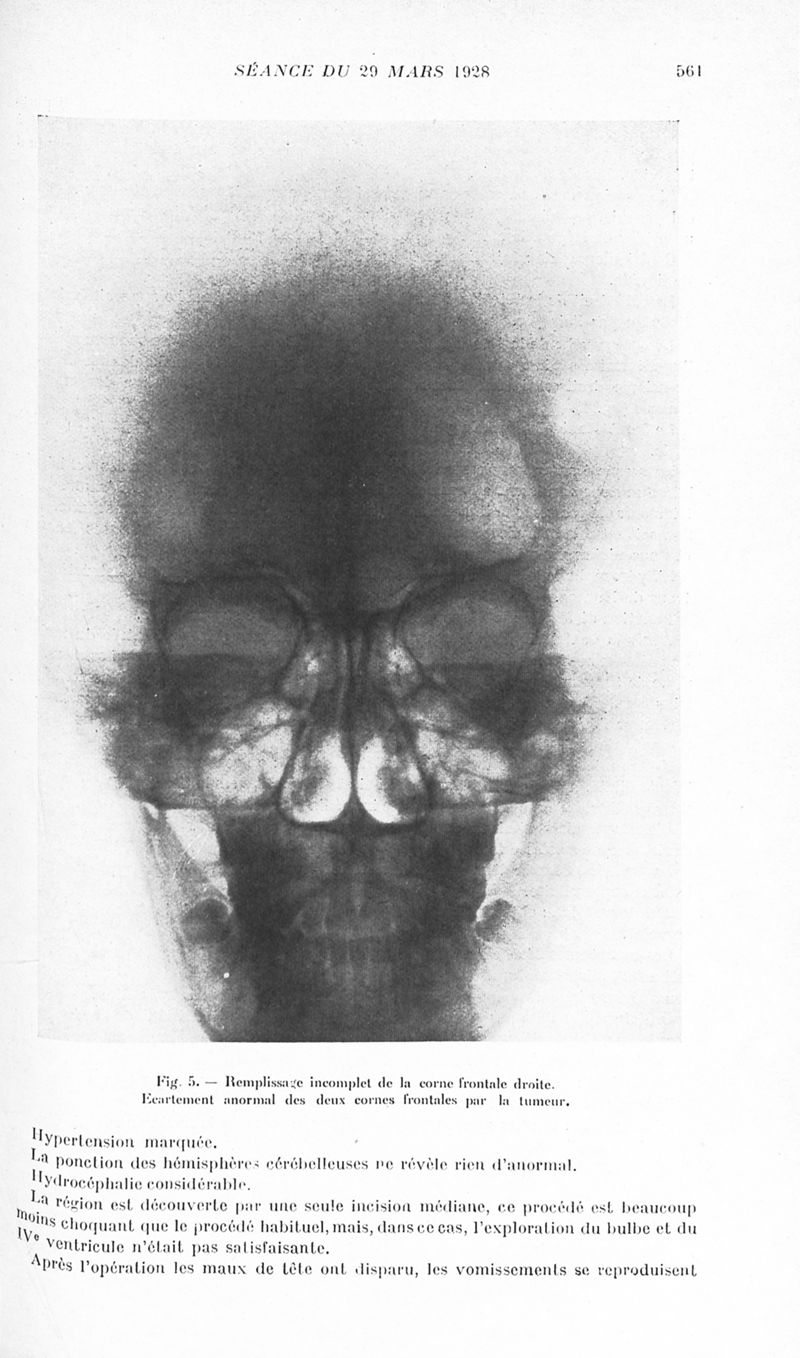

Revue neurologique

1928, vol 1. - Paris : Masson , 1928.